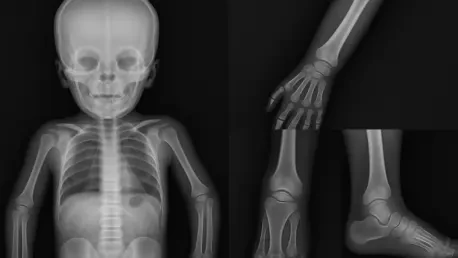

In the intricate world of pediatric radiology, one of the most pressing challenges is determining whether certain bone features in children, specifically in the metaphyseal regions of the distal femurs and proximal tibias, represent normal growth variations or indicate serious pathological lesions. These areas, located near the ends of long bones, are critical zones of development in young patients, and their appearance on imaging can often be misleading. A normal variation might resemble a lesion caused by trauma, metabolic disease, or even malignancy, leading to potential misdiagnosis. This confusion can have profound consequences, ranging from unnecessary stress and medical interventions to delayed treatment of genuine conditions. Recent research has delved into this complex issue, aiming to refine diagnostic accuracy by better understanding the nuances of bone morphology in children. The ability to distinguish between harmless variations and concerning lesions is not just a technical challenge but a vital step toward improving health outcomes for young patients facing skeletal uncertainties.

Distinguishing between normal metaphyseal variations and pathological lesions in children’s bones is a task fraught with difficulty due to the dynamic nature of skeletal growth. The metaphyseal regions of the distal femur and proximal tibia are particularly prone to variability as they play a central role in bone lengthening during childhood. Factors such as age, sex, and individual developmental patterns contribute to a wide range of appearances on imaging studies, which can closely mimic signs of serious conditions like fractures or metabolic disorders. Studies underscore the importance of recognizing these normal differences to prevent diagnostic errors. Without a clear framework for identifying what falls within the spectrum of typical growth, radiologists risk misinterpreting harmless features as alarming abnormalities, potentially subjecting young patients to undue stress and medical scrutiny. This highlights a critical gap in current practices that recent research seeks to address through detailed analysis of bone morphology.

Advancements in imaging technology have emerged as powerful allies in the effort to differentiate metaphyseal variations from lesions, offering unprecedented detail in the analysis of bone structure. High-resolution scans and quantitative assessment tools enable radiologists to examine the intricacies of the distal femur and proximal tibia with greater accuracy than ever before. These innovations reveal subtle textural and structural differences that can help distinguish a benign variation from a concerning abnormality, reducing the likelihood of misinterpretation. Research highlights that integrating such cutting-edge tools into routine practice is essential for elevating diagnostic standards in pediatric radiology. The enhanced visibility provided by modern imaging not only aids in identifying normal growth patterns but also builds confidence among clinicians tasked with making critical decisions. As technology continues to evolve, its role in refining the diagnostic process becomes increasingly indispensable for ensuring young patients receive the most accurate assessments possible.

Beyond the capabilities of advanced imaging, the development of age-specific diagnostic guidelines represents a crucial step toward addressing the variability inherent in children’s bone growth. Skeletal development does not follow a uniform timeline, meaning that what appears atypical in one age group might be entirely expected in another. Tailored references that account for these developmental stages provide radiologists with a contextual framework for interpreting imaging results, ensuring that findings are evaluated against appropriate benchmarks. Studies suggest that such guidelines can significantly reduce diagnostic ambiguity by aligning assessments with the natural progression of bone maturation. This approach acknowledges the diversity of growth patterns among children and emphasizes the importance of customization in medical diagnostics. By adopting age-specific standards, the field moves closer to a model of care that prioritizes precision and minimizes the risk of over- or under-diagnosis in pediatric skeletal evaluations.